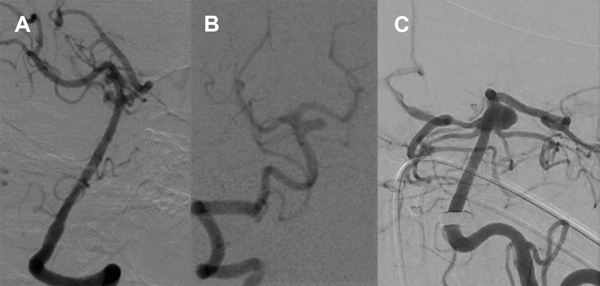

Figura 6. Paciente 15, caso 16. A y B, DSA pre embolización, aneurisma de SCA izquierda tipo PCA- SCA; C, abordaje de SCA izquierda desde PComA- P1 derecha; D, inicio de coiling tras implantar Neuroform Atlas 3 x 21 y Lvis 3.5 x 17; E- F, DSA post embolización, R-R 1; G, control a los 13 meses.

La series angiográfícas de control muestran adecuada oclusión del aneurisma y buena perfusión en todos los territorios, prestando especial atención a las ramas involucradas en el implante  de stents. La paciente se mantiene asintomática, actualmente antiagregada sólo con aspirina, y la DSA a 14 meses confirma oclusión completa (RR 1) (figura 6).

Paciente mujer de 60 años con diagnóstico incidental de aneurismas múltiples, con un aneurisma de mayor tamaño de forma ampular sobre el tronco basilar, en el segmento de cerebelosa superior izquierda, cuyo diámetro es de 6.3 de ancho y 5 mm de altura con cuello de 6.6 mm (AR 0.75, DNR 1), orientado hacia afuera y que eleva el origen de la arteria cerebral posterior izquierda e involucra el origen de la arteria cerebelosa superior izquierda.

Se tomó un doble abordaje con vaina carotídea Shuttle 7F que se posiciona en segmento ascendente de la arteria subclavia izquierda y catéter Guider 6F a segmento suprabulbar de carótida interna derecha. Por este último se navega un microcatéter Excelsior SL10 sobre guía Transend 0.014”, avanzando por la arteria comunicante posterior que es de buen tamaño hacia el segmentoP1 derecho en forma retrógrada y luego se utiliza una guía Hybrid 0.007” para avanzar selectivamente en la arteria cerebelosa superior izquierda.

Dejando este microcatéter posicionado, se asciende con otro microcatéter  SL10 por arteria vertebral izquierda y tronco basilar hasta la cavidad aneurismática, y se asegura la posición insinuando un asa de coil.

En paralelo por el mismo acceso se progresa un tercer microcatéter, en este caso Headway21, avanzado hasta segmento P2 de la arteria cerebral posterior izquierda.

A través del SL10 ubicado en arteria cerebelosa superior izquierda se implanta un stent de malla semi abierta Neuroform Atlas 3 x 15mm, cruzando el tronco basilar hacia el segmento P1 derecho, logrando correcta expansión y con controles satisfactorios en ambas arterias.

Como segundo paso, a través del microcatéter Headway21 se implanta un stent autoexpandible de malla cerrada Lvis de 3.5 x 17mm, descendiendo desde cerebral posterior izquierda por el tronco basilar con buena expansión sobre el mismo y cubriendo toda la extensión del cuello del aneurisma.

Por último, a través del SL10 posicionado en la cavidad aneurismática se inicia la embolización implantando sucesivos microcoils de platino hasta lograr un ovillo compacto que ocupa toda la malformación.